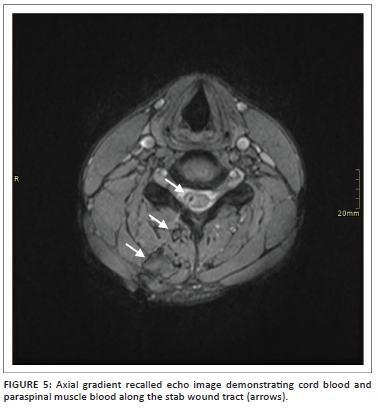

In our study, the majority (94.6%) of the patients had T2-weighted sagittal imaging, while 91.1% of cases had sagittal T2 STIR included. Even though T1- and T2-axial imaging does not serve prognostication purposes,11 it does aid in deciding whether haematoma is intra- or extra-axial. In our experience, cord laceration was best depicted on T2 STIR sagittal images (Figure 3), while fluid collections were best seen on T2 STIR and T2 sagittal images (Figure 4). Gradient recalled echo images were the best at depicting cord haemorrhage (Figure 5) although without spinal X-rays and CT, there is difficulty in differentiating intra-spinal air and foreign fragments (Figure 6) from haemorrhage.